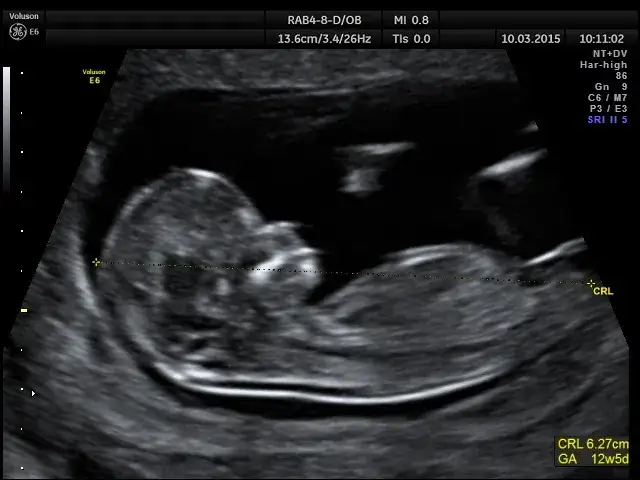

W pierwszym trymestrze ciąży, zazwyczaj między 6. a 13. tygodniem, podczas badania USG lekarz wykonuje pomiar długości ciemieniowo-siedzeniowej płodu, czyli tzw. pomiar CRL (Crown-Rump Length). Jest to odległość od czubka głowy do końca tułowia dziecka. Dlaczego jest to tak istotne? Ponieważ na tym etapie rozwoju wszystkie płody rosną w bardzo podobnym tempie, niezależnie od genetyki czy innych czynników. Dzięki temu pomiar CRL jest uznawany za "złoty standard" w ocenie wieku ciążowego i jest najbardziej dokładną metodą jego ustalenia. Pozwala on na precyzyjne określenie terminu porodu z marginesem błędu wynoszącym zaledwie kilka dni.

Zdarza się, że obliczenia na podstawie daty ostatniej miesiączki różnią się od tych uzyskanych z pomiaru CRL. Kiedy taka sytuacja ma miejsce, lekarze zawsze kierują się wynikiem badania USG. Przyjmuje się, że jeśli różnica między wiekiem ciąży z OM a wiekiem z USG przekracza 5-7 dni, za bardziej wiarygodny i ostateczny uznaje się wynik badania USG. Dzieje się tak, ponieważ pomiar CRL w pierwszym trymestrze jest niezwykle precyzyjny i pozwala skorygować ewentualne niedokładności wynikające np. z nieregularnych cykli czy późniejszej owulacji.